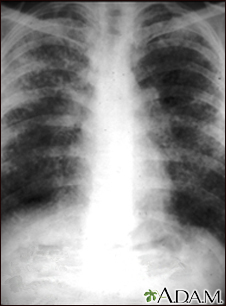

Sarcoid, stage II - chest x-rayBackSarcoid, stage II - chest x-raySarcoid causes damage to the lung tissue that heals by scarring. The film shows a diffuse milky and granular appearance in the normally dark lung areas. This individual has marked decrease in lung function. E-mail FormEmail ResultsName:Email address:Recipients Name:Recipients address:Message: